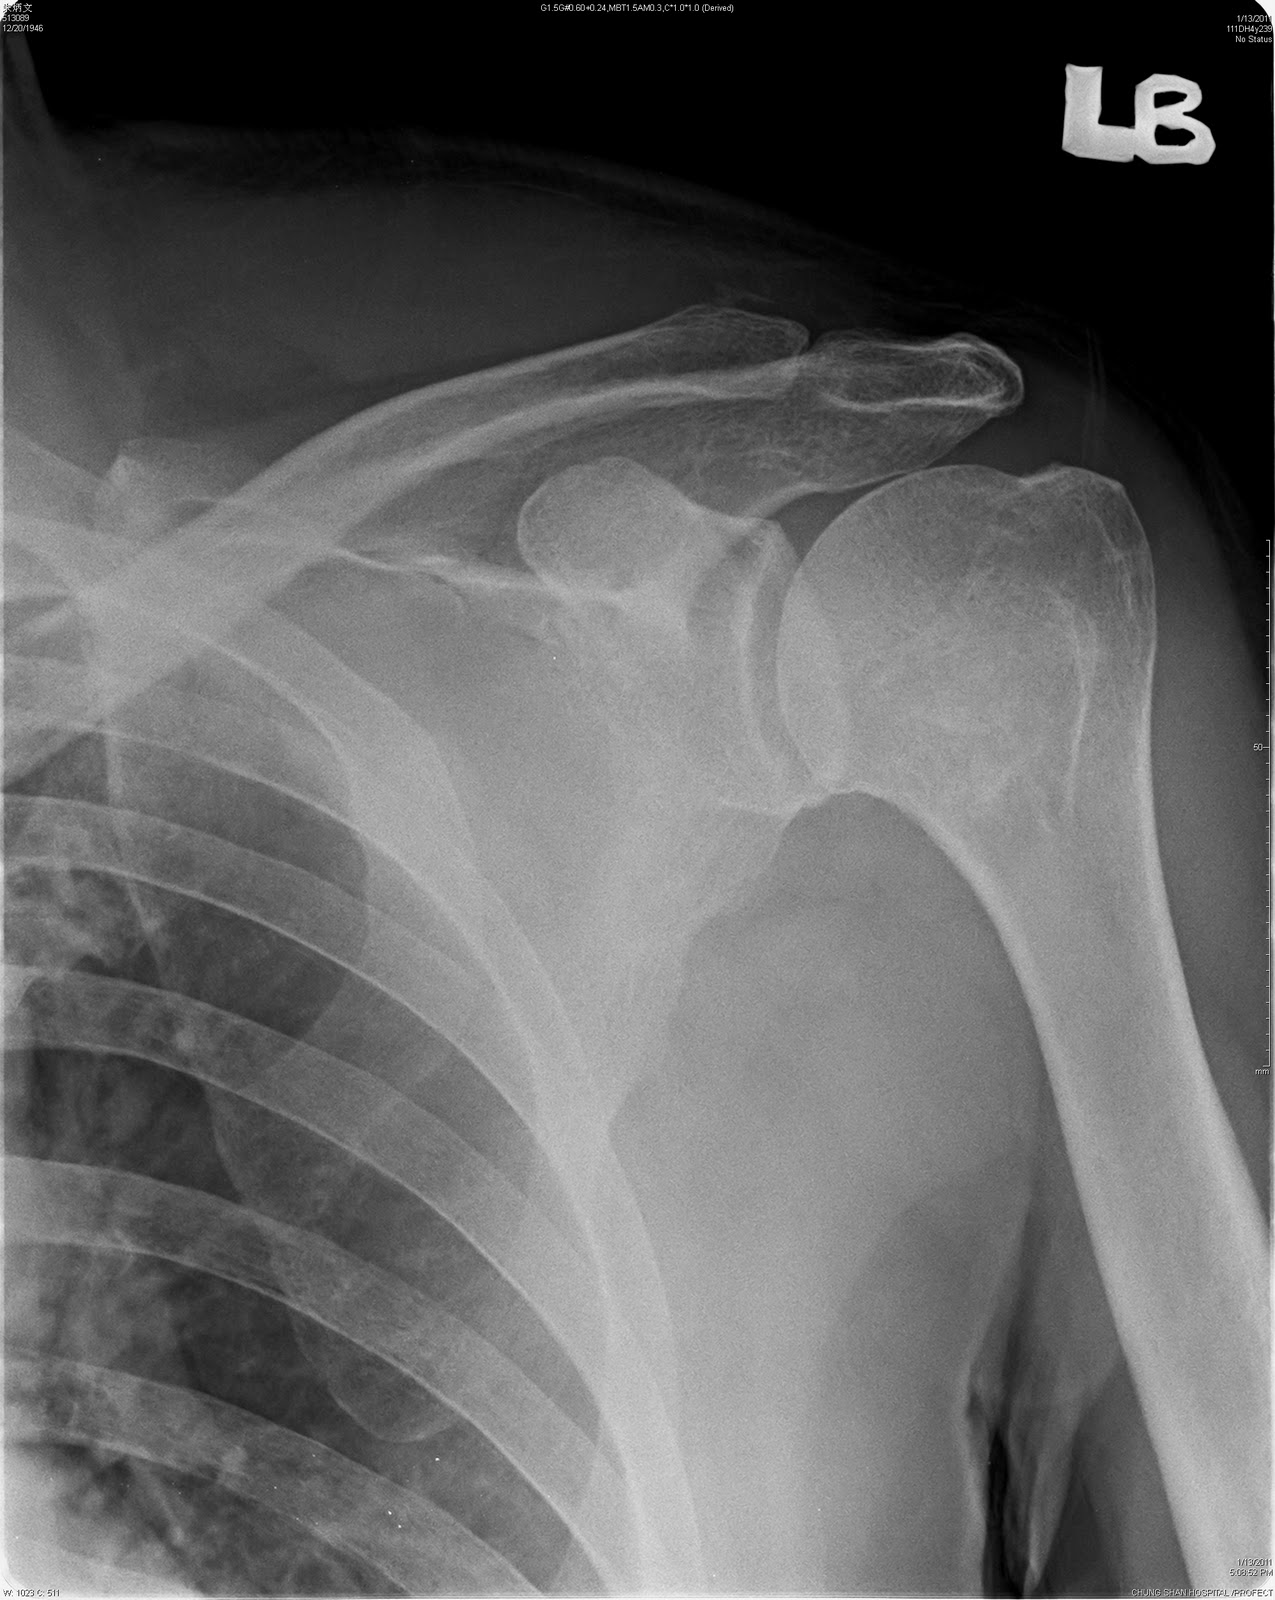

- X-rays: Usually the first imaging test performed, providing a two-dimensional view of the bones

Whether or not a physical exam is possible, your doctor will also order imaging tests of your shoulder and chest. They may order X-rays or a CT scan to determine exactly where and how badly your shoulder blade was broken.

- Radiography . It is the main method of instrumental diagnostics. For most fractures, radiographs of the scapula are performed in frontal and lateral projections. If the glenoid cavity is damaged, an x-ray of the shoulder joint is shown.